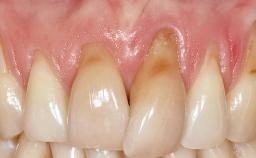

Periodontal Plastic Surgery and Prosthetic Procedures to Treat Peri-Implant Soft-Tissue Dehiscences

A 30-year-old woman was referred by her general dentist for evaluation of an esthetic complication related to previous implant treatment for congenitally missing maxillary lateral incisors. The patient’s chief complaint was the inadequate esthetic appearance of her smile. The case demonstrates the use of a combined approach to achieve optimal results. Two different flap designs - a tunnel technique and a coronally advanced flap - are employed based on the surgical objectives for the affected site.

Soft Tissue Anatomy Intact Defective

Soft Tissue Contour and Volume Slightly compromised